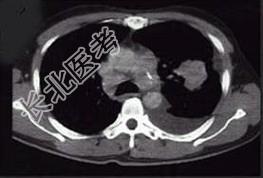

- 单项选择题女,68岁, 咳嗽伴胸痛胸闷一月,CT检查如图, 最可能的诊断为 ( )

A、左上肺不张

B、左上肺周围型肺癌伴胸膜转移

C、左上肺血管瘤

D、左上肺软骨肉瘤伴胸膜转移

E、左上肺结核